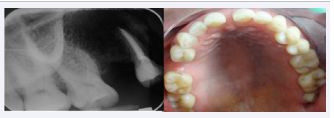

Ten days after the patient attends follow-up appointment and root canal treatment. Clinically showed a slight bruising on the right side (Figure 3),

Ten days after hypochlorite accident.

Figure 3 Ten days after hypochlorite accident.

but no pain nor paraesthesia. Radiographically changes were not observed, and root canal treatment was concluded using NaClO 2.5% and biomechanical ProTaper® NiTi rotary instrumentation (Dentsply-Maillefer, Switzerland). For the final procedure, sterile saline solution 0.9% (PiSA®, Mexico) was used for irrigation. Conducts were dried before and after the use of EDTA 17% (Densell, Argentina) during three minutes, and filled and sealed with Hygienic® Gutta Percha points caliber 35 and cement calcium hydroxide-based Sealapex® (SybronEndo, EUA) using a modified ultrasonic side technique (Figure 4).

Obturation radiography; lateral technique with ultrasonic  scale.

Figure 4 Obturation radiography; lateral technique with ultrasonic scale.